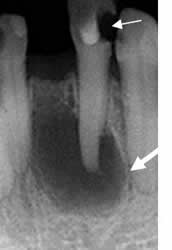

Fig 51 B. Osteitis periapical.

A y B: Rx periapical. Aumento del espacio periapical, por enfermedad periodontal. Los bordes son escleróticos, por evolución crónica. En B se aprecia aumento de la densidad en la cresta alveolar, por osteitis esclerosante.